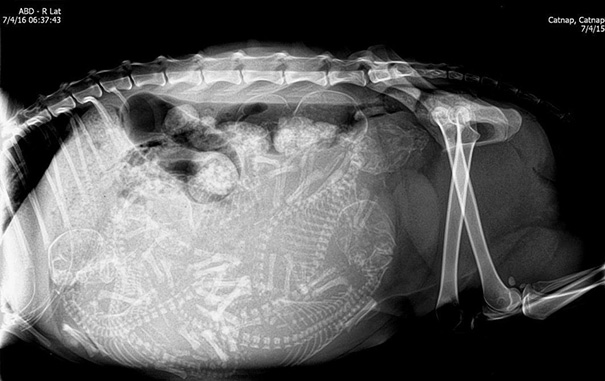

X-Ray Of A Pregnant Turtle

This is my image!! Follow me on instagram @taz_photo_ . Working on putting a website together :)

It came in missing it's front leg! We don;t know why.

We Just Found Out That One Of Our Transmitted Tortoises Is Pregnant